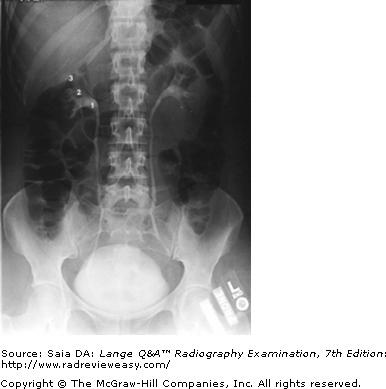

Free air in the abdominal cavity is demonstrated in

which of the following?

1. Lateral recumbent abdomen

2. Erect AP abdomen

3. Left lateral decubitus abdomen

2 and 3 only

Which projection(s) of the abdomen would be used to

demonstrate pneumoperitoneum?

1. Right lateral decubitus

2. Left lateral decubitus

3. Upright